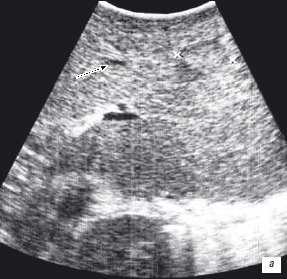

Особенностью проведения интраоперационного ультразвукового исследования у пациентов с первичным поражением печени является то, что гепатоцеллюлярный рак часто развивается на фоне цирроза печени. Следовательно, если опухоль локализуется в толще паренхимы, а так же имеет не большие размеры, пальпаторно определить ее границы крайне затруднительно. Таким образом, задачи установленные перед интраоперационной ультразвуковой томографией были несколько иными, а именно: определение границ опухоли, разметка зоны резекции, определение связи с магистральными сосудами (рис. 2 а,б).

Рис. 2. Метастатические очаги (стрелки) в печени на фоне цирроза.

Клинический пример N3. Пациент Ш. находился на лечении в ГУ РОНЦ РАМН с диагнозом гепатоцеллюлярный рак. При проведении стандартного ультразвукового исследования в правой доле печени было выявлено образование, занимающее практически всю правую долю, с четкими, неровными контурами. На операции пальпаторно определить границу опухоли и неизмененной ткани не представлялось возможным. При проведении интраоперационного ультразвукового исследования была обозначена граница опухолевого образования и неизмененной паренхимы и соотношение этого образования с сосудами печени.